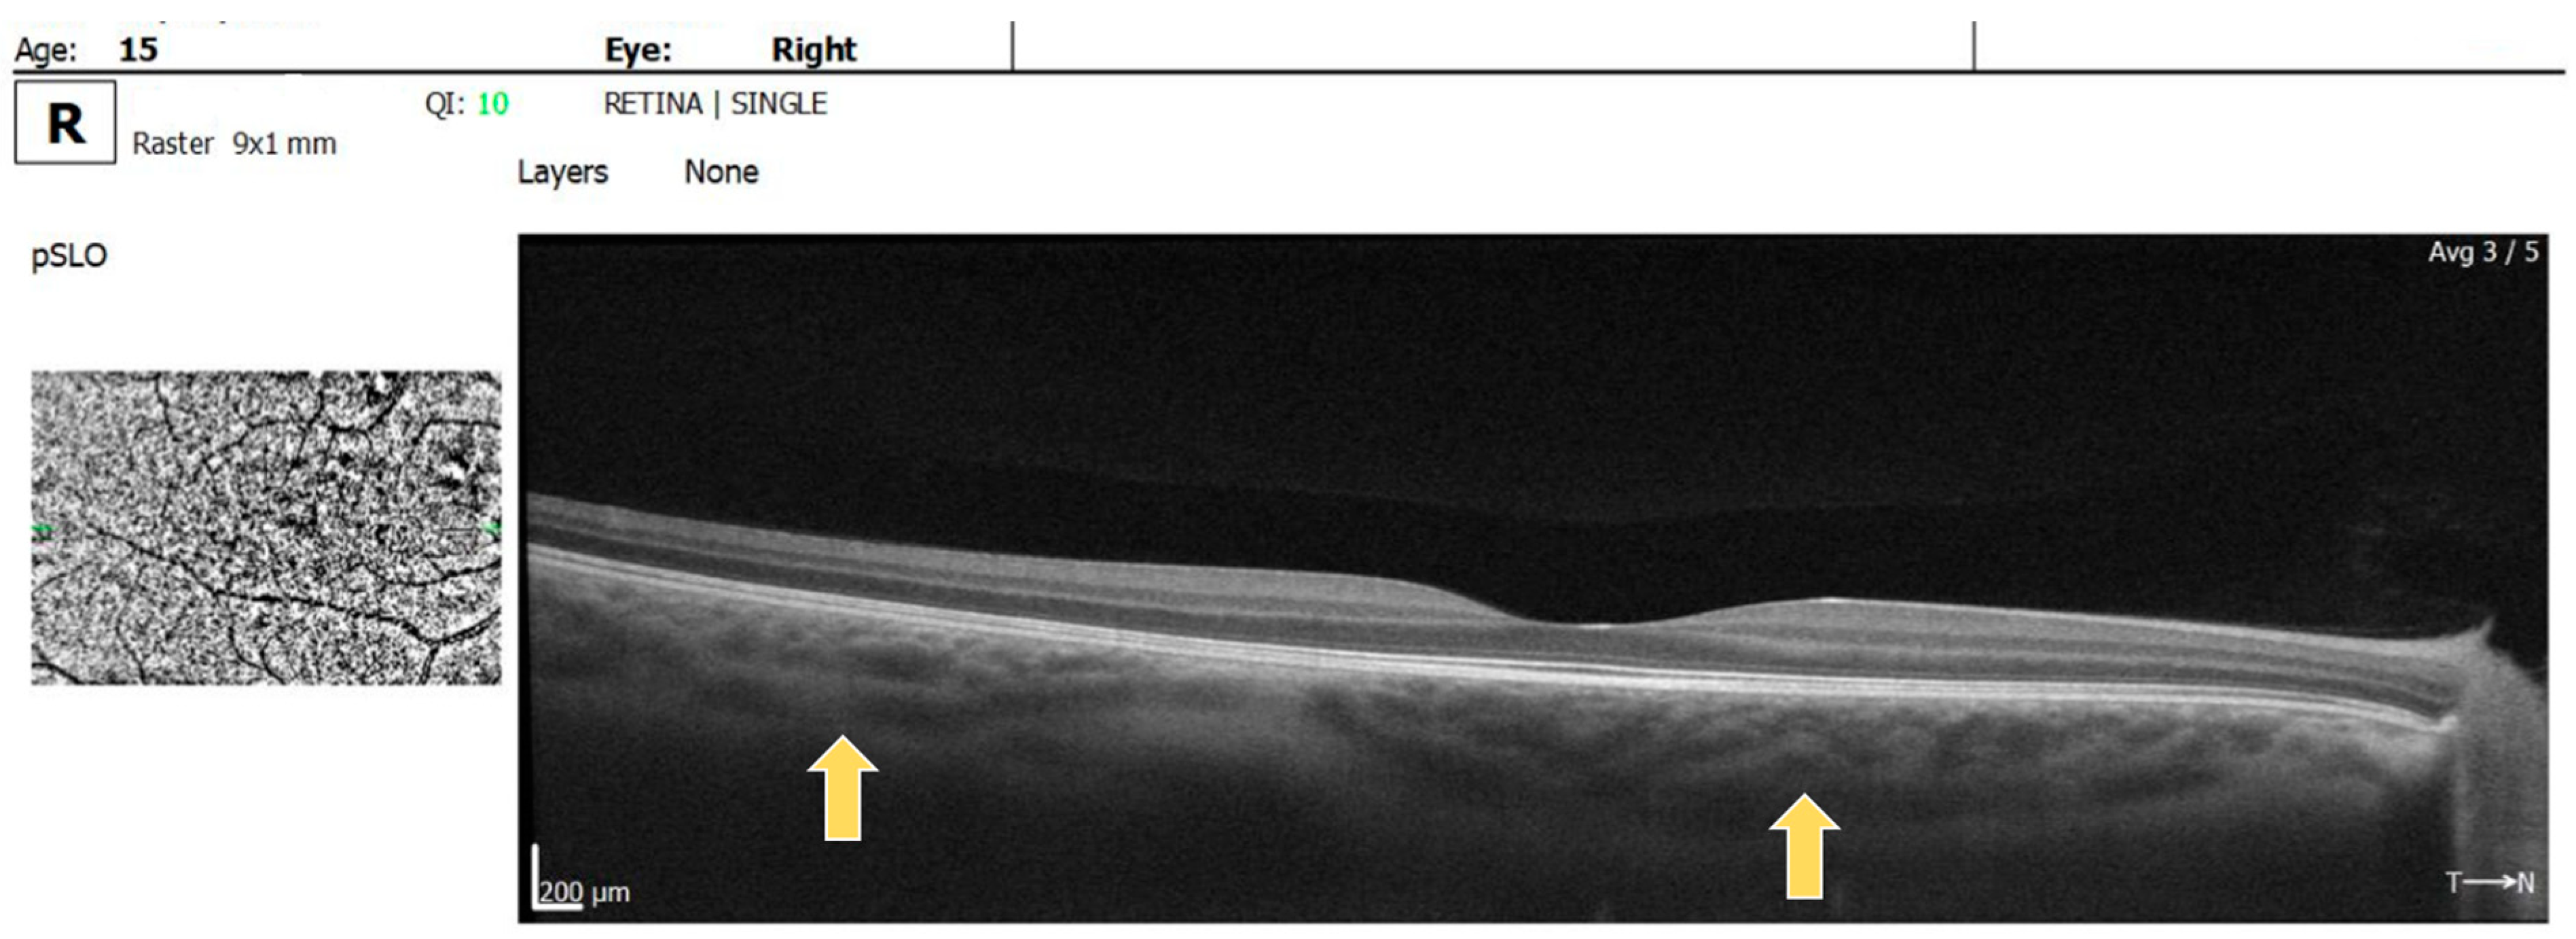

2. Case Report